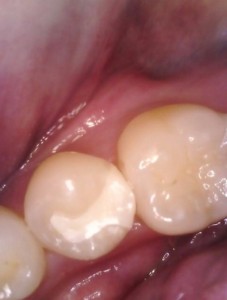

2日目 ジルコニアインレーを接着性セメントで装着しました。

治療後の様子

患者様からは、「右下の破損した歯に痛みを感じることはなかったけれど、検診に来て早く気付けたことに安心した」とのお言葉をいただきました。